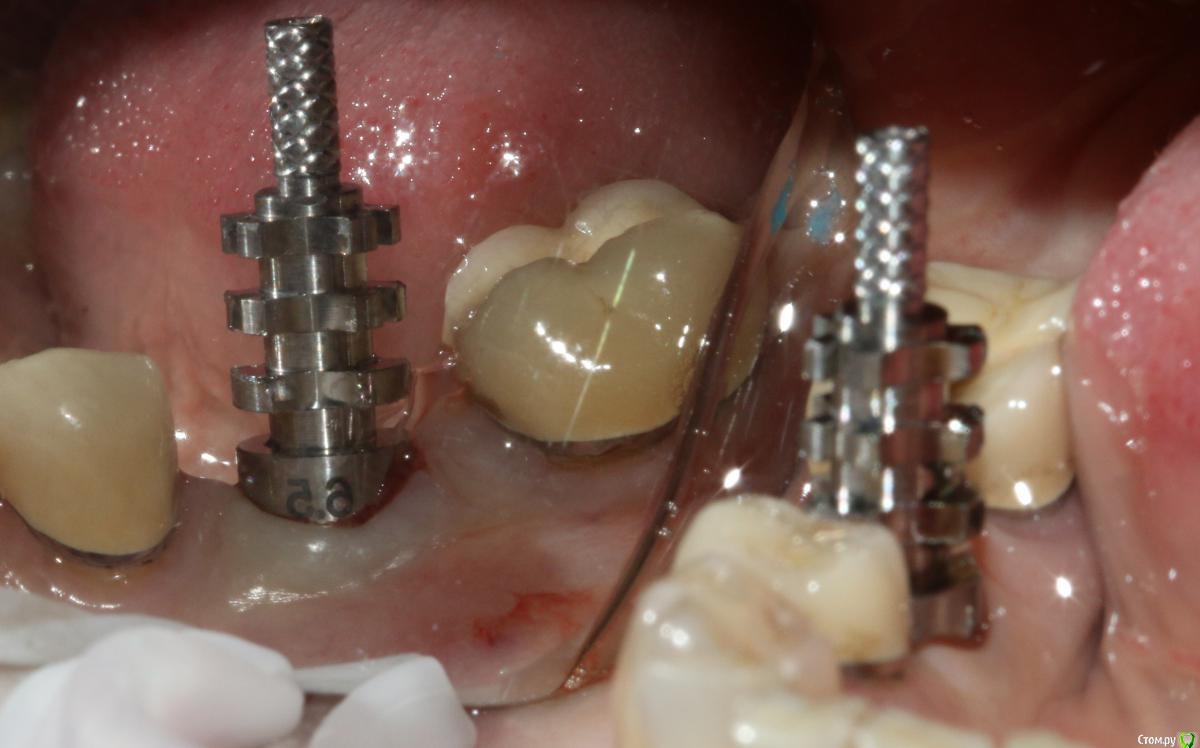

Ильдар Опубликовано 29 марта, 2015 Поделиться Опубликовано 29 марта, 2015 Коллеги, здравствуйте!Вот демонтировал старье. мк на зубы.имплант 4310, поставил поглубже.мк на имплант - техник прислал коронку с шахтой и абатмент,я склеил на fuji1. закрутил на 35 н.залепил не очень красиво , но с плавиковой, силаном и олбонд 3. думаю надежно.контрольный прицельный есть, видимо забыл его. извиняюсь за нечеткие fото. буду рад отзывам 3 Ссылка на комментарий

molchanoff Опубликовано 29 марта, 2015 Поделиться Опубликовано 29 марта, 2015 техник прислал коронку с шахтой и абатмент,я склеил на fuji1. закрутил на 35 н. чет не понятно у вас винтовая или цементная фиксация? Ссылка на комментарий

Ильдар Опубликовано 29 марта, 2015 Автор Поделиться Опубликовано 29 марта, 2015 чет не понятно у вас винтовая или цементная фиксация? техник начинал делать цементную. после литья каркаса я его попросил модиицировать под винтовую. он сделал отверстие в коронке, облицевал, заполировал. я склеил абатмент и коронку в руках, закрутил в рот. Ссылка на комментарий

molchanoff Опубликовано 29 марта, 2015 Поделиться Опубликовано 29 марта, 2015 техник начинал делать цементную. после литья каркаса я его попросил модиицировать под винтовую. он сделал отверстие в коронке, облицевал, заполировал. я склеил абатмент и коронку в руках, закрутил в рот.а зачем? 1 Ссылка на комментарий

bugel Опубликовано 30 марта, 2015 Поделиться Опубликовано 30 марта, 2015 Наверно основание абатмента глубоко под десневой части, чтобы цемента не было после фиксации- периимплантита в будущем, поэтому перевёл в винтовую. Ссылка на комментарий

Ильдар Опубликовано 30 марта, 2015 Автор Поделиться Опубликовано 30 марта, 2015 Наверно основание абатмента глубоко под десневой части, чтобы цемента не было после фиксации- периимплантита в будущем, поэтому перевёл в винтовую.Да Ссылка на комментарий

АнтонТЛТ Опубликовано 30 марта, 2015 Поделиться Опубликовано 30 марта, 2015 чет не понятно у вас винтовая или цементная фиксация? SCRP screw-cement retained prosthesis (цементно-винтовая фиксация) Ссылка на комментарий